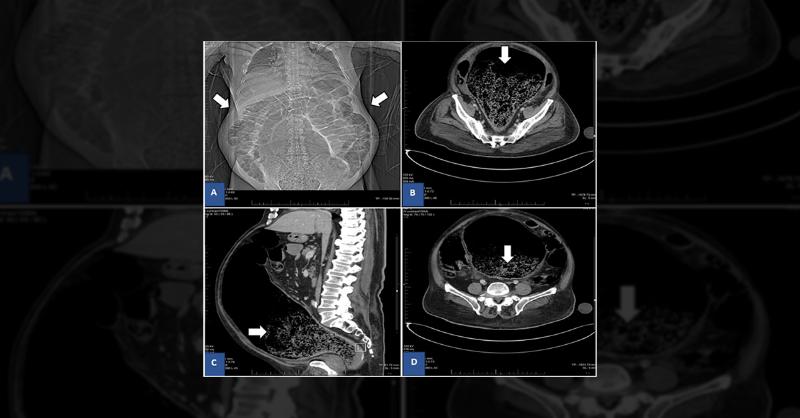

A 78-year-old man with a history of hypertension, diabetes, and a recent delusional disorder presented with abdominal pain, poor appetite, and constipation. Under psychiatric care, he had been prescribed risperidone and procyclidine. Despite experiencing minor constipation episodes, his symptoms were generally controlled. In the emergency departmen